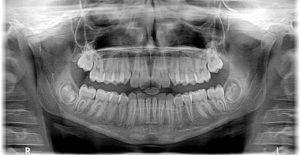

xray-x-ray-2764828_1280-1StartseiteMedizinKieferbruch: Die häufigste Fraktur im Kopfbereich 3. Juni 2021 0 5 Jahren Beitrags-Navigation Vorheriger Beitrag Schreibe einen Kommentar Antwort abbrechenDu musst angemeldet sein, um einen Kommentar abzugeben.